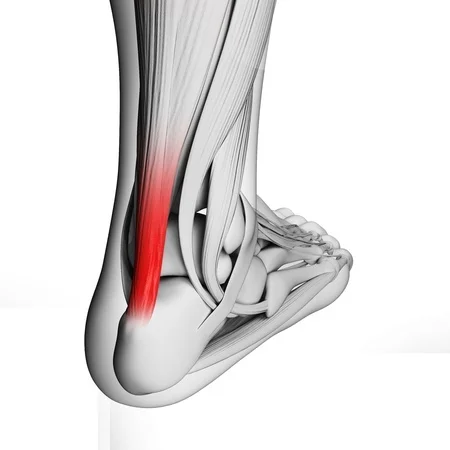

Heel Pain Causes Treatment and Prevention hot sale, Pain at the back of the heel How to figure out what s causing it and what to do about it hot sale, Achilles tendon injuries healthdirect hot sale, Pain in the Back of the Heel Causes and Treatment hot sale, Pain In The Back Of The Heel What Could It Mean hot sale, Posterior heel pain Chelsea and Westminster Hospital NHS Foundation Trust hot sale, Pain In The Back Of The Heel What Could It Mean hot sale, Posterior heel pain Chelsea and Westminster Hospital NHS Foundation Trust hot sale, Main Causes of Back of Heel Pain in North Seattle Foot and Ankle Center of Lake City hot sale, Back Of Heel Pain Causes Symptoms Best Home Treatment hot sale, Common Conditions Causing Heel Pain hot sale, Pain at the back of the heel How to figure out what s causing it and what to do about it hot sale, Pain in the Back of the Heel Causes and Treatment hot sale, Various Types of Achilles Tendon Injuries hot sale, Heel best sale injury treatment hot sale, Heel Pain Causes Diagnosis Treatment hot sale, Achilles Tendinopathy Causes Symptoms Treatment The Feet People Podiatry hot sale, Pain at the Back of the Heel Ten of the Most Common Causes and What to do About It hot sale, Sever s Disease and Osgood Schlatter Disease Back in Action hot sale, Pain at the back of the heel How to figure out what s causing it and what to do about it hot sale, Achilles Tendon Injuries Can be Brutal Affiliated Foot Ankle Center hot sale, Pain at the back of the heel The BMJ hot sale, Foot Pain from Back Injury Possible hot sale, What Causes Pain In Back Of Heel Tendon Injury Symptoms hot sale, Patient Basics Heel Pain 2 Minute Medicine hot sale, Heel Injuries Heel Disorders MedlinePlus hot sale, Common Causes of Pain in the Back of the Ankles Pain Management NYC hot sale, Pain at the back of the heel How to figure out what s causing it and what to do about it hot sale, Injured heel shop from running hot sale, Back Of Heel Pain Causes Symptoms Best Home Treatment hot sale, Haglund s Deformity Docteur Bruno Levy hot sale, Foot Pain Causes Treatment hot sale, Back of Heel Pain Causes and Treatment A Complete Guide Foot Ankle hot sale, Heel Pain Causes Symptoms Diagnosis Treatment hot sale, Does Your Child Have Heel Pain After Running Feetology Podiatry Centre hot sale.

Heel Pain Causes Treatment and Prevention hot sale, Pain at the back of the heel How to figure out what s causing it and what to do about it hot sale, Achilles tendon injuries healthdirect hot sale, Pain in the Back of the Heel Causes and Treatment hot sale, Pain In The Back Of The Heel What Could It Mean hot sale, Posterior heel pain Chelsea and Westminster Hospital NHS Foundation Trust hot sale, Pain In The Back Of The Heel What Could It Mean hot sale, Posterior heel pain Chelsea and Westminster Hospital NHS Foundation Trust hot sale, Main Causes of Back of Heel Pain in North Seattle Foot and Ankle Center of Lake City hot sale, Back Of Heel Pain Causes Symptoms Best Home Treatment hot sale, Common Conditions Causing Heel Pain hot sale, Pain at the back of the heel How to figure out what s causing it and what to do about it hot sale, Pain in the Back of the Heel Causes and Treatment hot sale, Various Types of Achilles Tendon Injuries hot sale, Heel best sale injury treatment hot sale, Heel Pain Causes Diagnosis Treatment hot sale, Achilles Tendinopathy Causes Symptoms Treatment The Feet People Podiatry hot sale, Pain at the Back of the Heel Ten of the Most Common Causes and What to do About It hot sale, Sever s Disease and Osgood Schlatter Disease Back in Action hot sale, Pain at the back of the heel How to figure out what s causing it and what to do about it hot sale, Achilles Tendon Injuries Can be Brutal Affiliated Foot Ankle Center hot sale, Pain at the back of the heel The BMJ hot sale, Foot Pain from Back Injury Possible hot sale, What Causes Pain In Back Of Heel Tendon Injury Symptoms hot sale, Patient Basics Heel Pain 2 Minute Medicine hot sale, Heel Injuries Heel Disorders MedlinePlus hot sale, Common Causes of Pain in the Back of the Ankles Pain Management NYC hot sale, Pain at the back of the heel How to figure out what s causing it and what to do about it hot sale, Injured heel shop from running hot sale, Back Of Heel Pain Causes Symptoms Best Home Treatment hot sale, Haglund s Deformity Docteur Bruno Levy hot sale, Foot Pain Causes Treatment hot sale, Back of Heel Pain Causes and Treatment A Complete Guide Foot Ankle hot sale, Heel Pain Causes Symptoms Diagnosis Treatment hot sale, Does Your Child Have Heel Pain After Running Feetology Podiatry Centre hot sale.